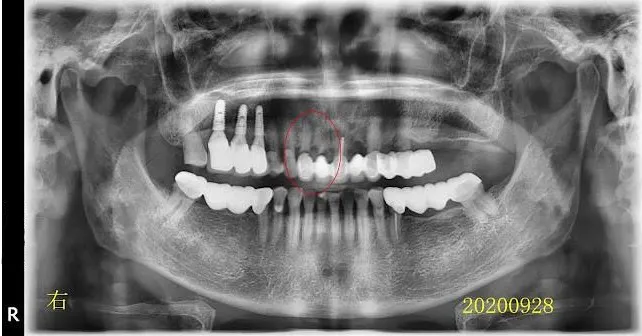

紅圈是非拔不可的牙齒,蛀到剩殘根(R.R.),這部分比較沒有異議。 牙齒殘根為何一定要拔?不拔會怎樣嗎? 我想很多人會有疑問,所以我問了M$的Copilot,AI的回答如下(令人汗顏,整理的真好,所以我直接複製貼上引用).... 本文的重點我想放在模擬治療計畫,順便說說智齒矯正取代。